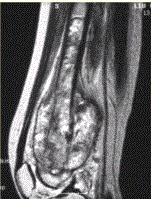

问题 患者男,16岁,左大腿下部疼痛伴肿胀2个月,逐渐加重。自感左膝上方胀痛,尤以夜间为著,伴行走困难。既往史及家族史无特殊。查体:左大腿下部明显肿胀,皮温较对侧升高。碱性磷酸酶明显增高。股骨平片及MRI见下图。 你认为对定性诊断有价值的征象是

选项 A.病变边缘模糊,内部信号不均 B.病变边缘骨皮质完整 C.病变周围可见软组织肿块 D.病变边缘可见骨膜反应,Codman三角形成 E.MR示病变周围骨髓明显水肿 F.病变内未见钙化影

答案 ACDEF